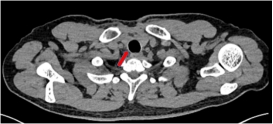

2. 纵隔肿瘤切除手术

纵隔肿瘤手术前 | 纵隔肿瘤手术后 |